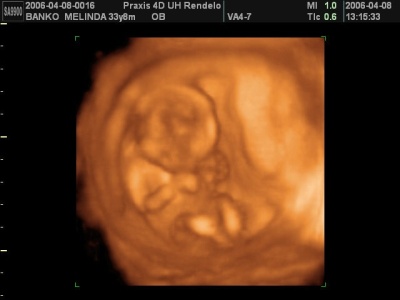

Én is csak javasolni tudom a 4d-s uh-ot, hihetetlen élmény!

Mi már kétszer voltunk, fantasztikus volt!

És szerintem még egyszer fogunk menni. Nincs nap, hogy ne nézném meg a dvd-felvételeket a kisemberünkről.

Mi a Praxisban voltunk, csak felsőfokon tudok nyilatkozni róluk.